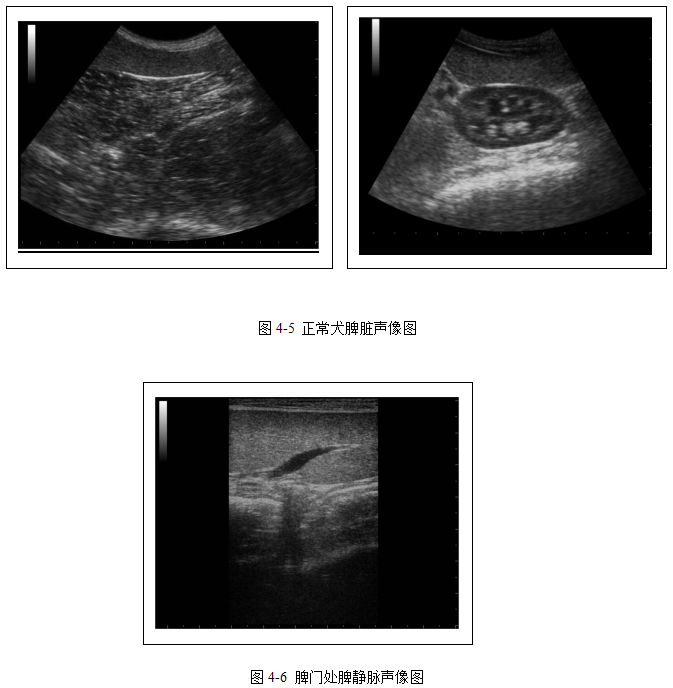

脾脏纵断面观呈伸长的舌状结构,横断面观呈三角形结构。犬脾脏的位置通常不固定,脾头位于偏背侧的位置,常在胃底和左肾之间形成“镰刀”样结构。脾实质为细腻均质的结构,脾脏包膜呈细的强回声线(图4-5)。与肝脏和肾皮质相比,通常脾实质的回声强度较高。脾静脉通常呈无回声的管状结构,位于脾实质中从脾门处伸出(图4-6)。脾动脉通常难以显示。